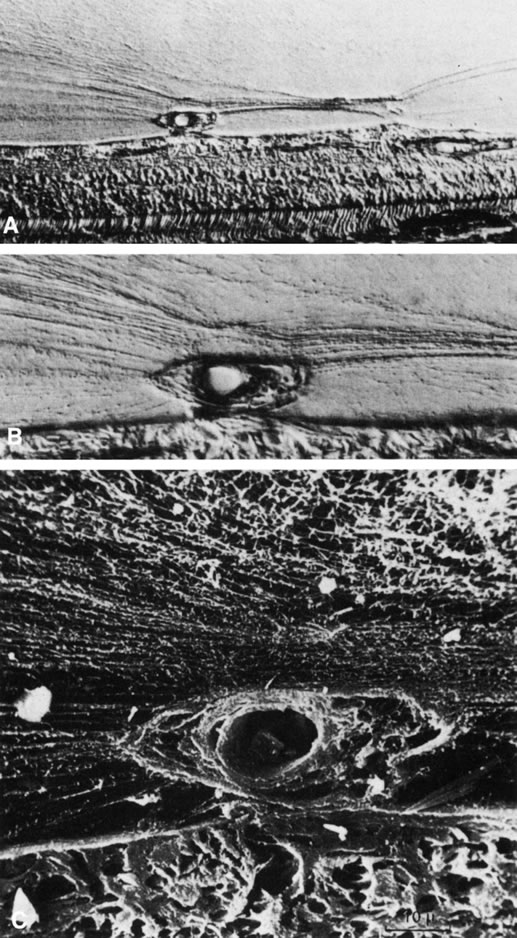

The embryonic vascular system of the vitreous (vasa hyaloidea propria) and lens (tunica vasculosa lentis) attains its maximum prominence during the ninth week of gestation or 40-mm stage.1 Atrophy of the vessels begins posteriorly with dropout of the vasa hyaloidea propria, followed by the tunica vasculosa lentis. Recent studies have detected the onset of apoptosis in the endothelial cells of the tunica vaculosa lentis as early as day 17.5 in the mouse embryo.2 At the 240-mm stage (seventh month) in the human, blood flow in the hyaloid artery ceases.3 Regression of the vessel itself begins with glycogen and lipid deposition in the endothelial cells and pericytes of the hyaloid vessels.3 Endothelial cell processes then fill the lumen, and macrophages form a plug that occludes the vessel. The cells in the vessel wall then undergo necrosis and are phagocytized by mononuclear phagocytes.4 Gloor5 claimed that macrophages are not involved in vessel regression within the embryonic vitreous but that autolytic vacuoles form in the cells of the vessel walls, perhaps in response to hyperoxia. Interestingly, the sequence of cell disappearance from the primary vitreous begins with endothelial and smooth muscle cells of the vessel walls, followed by adventitial fibroblasts and lastly phagocytes,6 consistent with a gradient of decreasing oxygen tension. Recent studies have suggested that the vasa hyaloidea propria and the tunica vasculosa lentis regress via apoptosis.7 These studies concluded that macrophages are important in this process. Subsequent studies by a different group confirmed the importance of macrophages in promoting regression of the fetal vitreous vasculature and further characterized these macrophages as hyalocytes.8

It is not known what stimulates regression of the hyaloid vascular system, but studies have identified a protein native to the vitreous that inhibits angiogenesis in various experimental models.9–11 Activation of this protein and its effect on the primary vitreous may be responsible for the regression of the embryonic hyaloid vascular system as well as the inhibition of pathologic neovascularization in the adult. Mitchell and colleagues12 point out that the first event in hyaloid vasculature regression is endothelial cell apoptosis and propose that lens development separates the fetal vasculature from vascular endothelial growth factor (VEGF)-producing cells, decreasing the levels of this survival factor for vascular endothelium, inducing apoptosis. Following endothelial cell apoptosis, there is loss of capillary integrity, leakage of erythrocytes into the vitreous, and phagocytosis of apoptotic endothelium by hyalocytes. Meeson and colleagues13 proposed that there are actually two forms of apoptosis that are important in regression of the fetal vitreous vasculature. The first (“initiating apoptosis”) results from macrophage induction of apoptosis in a single endothelial cell of an otherwise healthy capillary segment with normal blood flow. The isolated dying endothelial cells project into the capillary lumen and interfere with blood flow. This stimulates synchronous apoptosis of downstream endothelial cells (“secondary apoptosis”) and ultimately obliteration of the vasculature. Removal of the apoptotic vessels is achieved by hyalocytes.